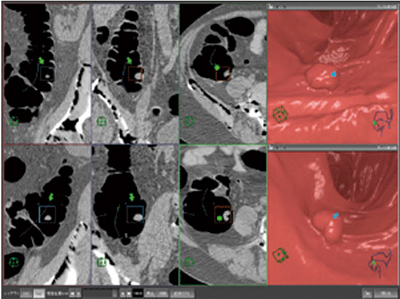

厚生労働省の人口動態統計では,わが国の大腸がん死亡率は,女性では2004年から胃がんを抜いてがん死因の1位になり,男性では肺がん,胃がんについで3位となった。術前検査として用いられることが一般的であった大腸3D-CT検査は,大腸がんスクリーニングへの拡大が期待され,これを補助するのに非常に有用なソフトウェアが“大腸解析ソフトウェア”である(図2)。

大腸解析ソフトウェアでは,大腸の自動抽出,フライスルーの自動検索を読み込みと同時に行ってくれるので,ユーザーは読影だけを行えばよい。残渣に埋もれたポリープを観察したいときは,電子クレンジング機能を用い,オリジナルの画像と電子クレンジングした画像を比較して確認することも可能である。また,2体位画像の同時比較が,随時に,かつ,素早く行え(図3),その画面でポリープなど観察したい箇所を指定するだけで,MPR像を簡単に作成でき,その病変の浸潤度を観察することが可能である。

結果の出力機能も充実しており,画像のDICOM保存,動画作成,レポート作成も一連の流れで行うことができる。

当社のネットワーク型ワークステーションを用いれば,大腸の自動抽出からフライスルー自動検索までと,読影を別々の場所で分担して行うことができ,ユーザーの負担を分散することが可能である。

図3 大腸解析の2体位同時表示